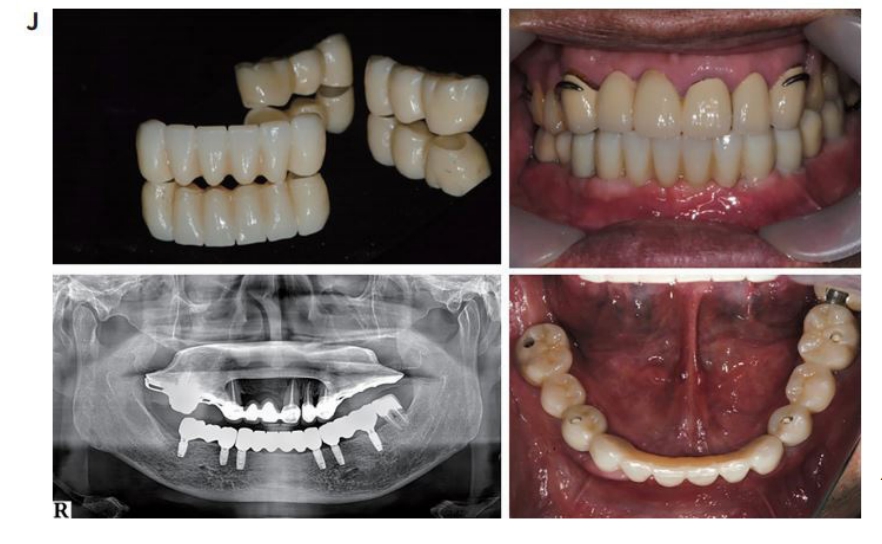

구강내 Scanning date Vertual wax-up date CT data를 융합하여 임플란트의 식립 위치, 방향을 결정하고 SurgiG uide를 제작하였다. SurgiGuide를 이용하여 임플란트를 식립하였으며, 1 주일 후에 stitch out 한 후 임시보철물을 위해 fixture에 scan body를 연결하고 seaming하여 PMMA 임시보철불을 제작하여 구강내에 장착하여 주었다.

일반적으로 single crown이나 적은 수의 임플란트 보철물은 Intraoral scanner에 의해 임시보철물, 최종보철물을 위한 digitlal impression을 할 수도 있으나 여러 개의 임플란트지지 보철물이나 Span이 긴 보철물일 경우에는 기존의 인상채득 방법에 의한 cast가 요구될 수 있다. 2개월 후에 인상채득하고 mounting jig를 이용하여 교합기에 모형을 mounting 한 후 Zirconia 최종보철물에 의한 치과보철수복을 하였다.